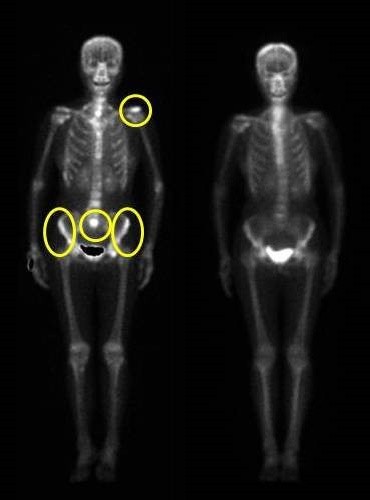

▲李女士標靶治療前後的骨骼掃描,黃圈顯示腫瘤轉移點。(圖/台北慈濟提供)

上述這位李女士沒有吸菸史,2009年確診肺腺癌第四期,左肺腫瘤轉移到骨頭且有胸腔積水。經過基因突變的檢測,表皮生長因子受體(EGFR)呈現陽性,適合以標靶藥物治療。2010年開始服藥,骨頭的癌細胞、胸腔積水逐漸消失,持續服藥至今,腫瘤縮小,而且幾乎沒有皮膚疹、腹瀉、甲溝炎等副作用,存活已超過7年。